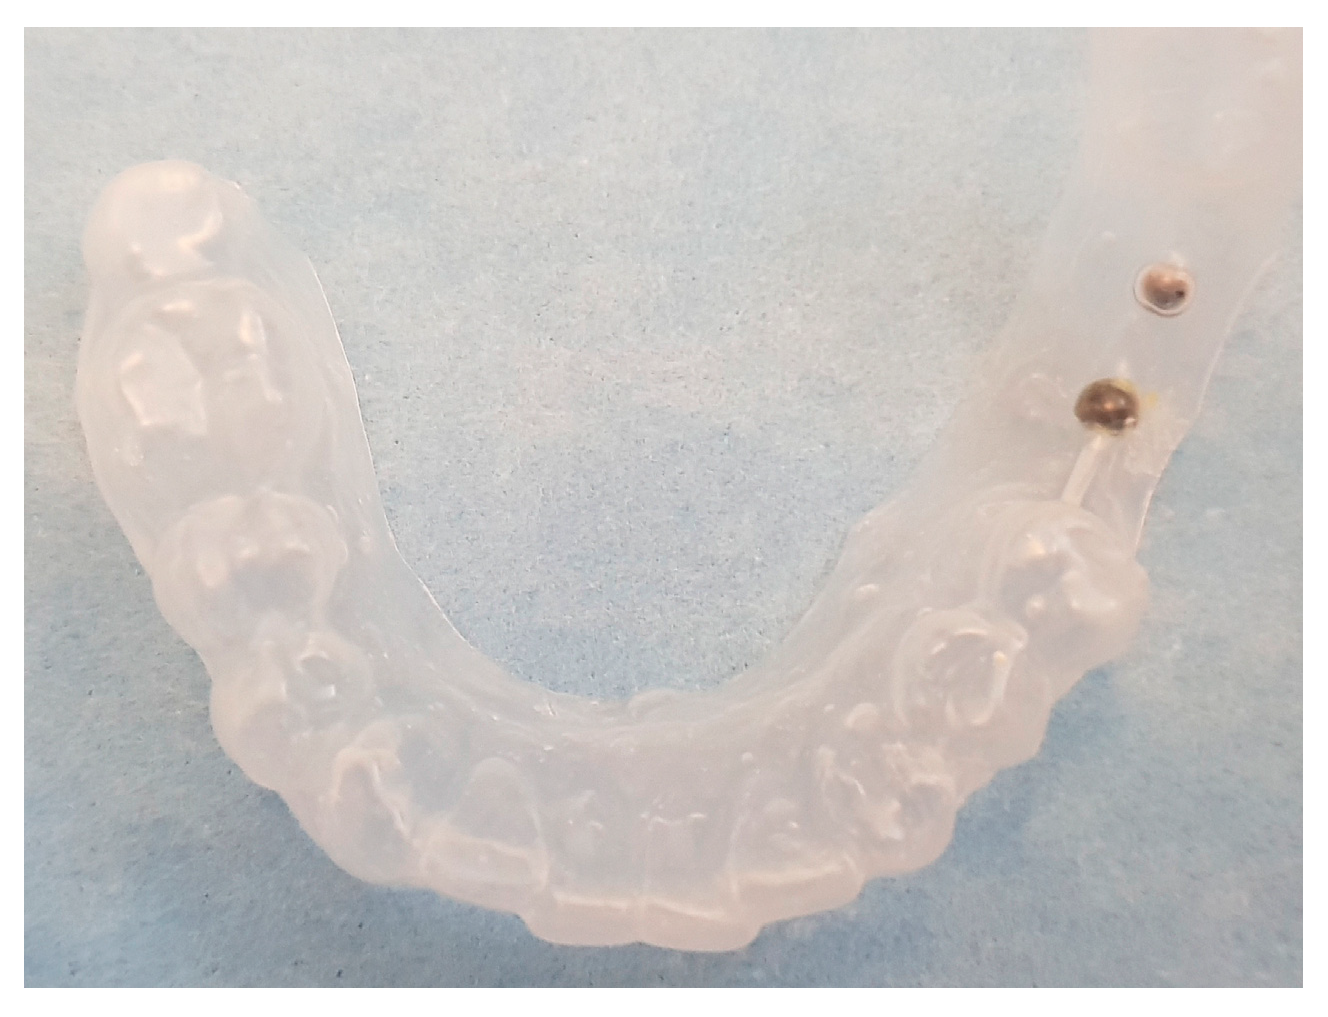

| Templates | 12 | 6 | 5 | 23 |

| Spheres | 12 | 12 | 15 | 39 |

Initial identification of hypothetical implant sites (panoramic radiograph) | Drawing (permanent marker) of the implant sites on a plaster cast | Template construction |

|

CBCT taken with template | Definitive patient selection Elegibility criteria: fixture position confirmed by CBCT |